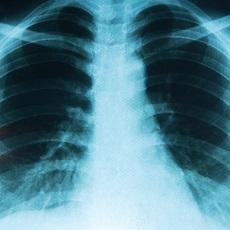

Lung cancer is cancer that forms in tissues of the lung, usually in the cells that line the air passages. It is the leading cause of cancer death in both men and women.

Lung cancer may not cause any signs or symptoms until the cancer is advanced. Sometimes the cancer is found during a chest x-ray done for another condition.

- May order certain imaging tests, such as a chest x-ray or chest CT scan